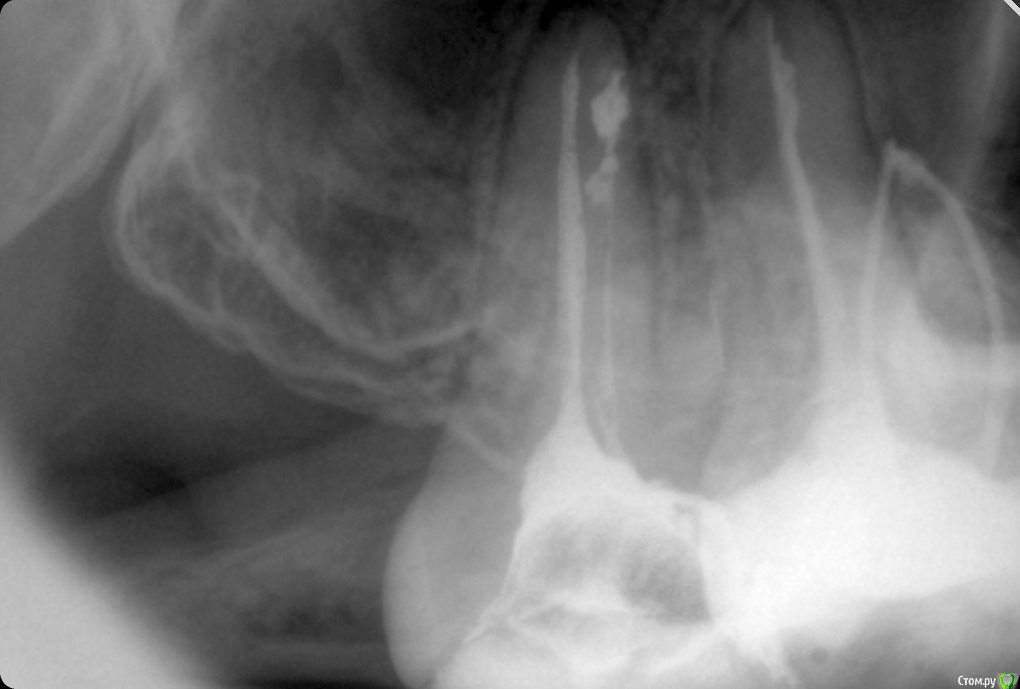

ozbourne87 Опубликовано 5 октября, 2018 Поделиться Опубликовано 5 октября, 2018 Добрый вечер! Подскажите причину боли в зубе(самый последний верхний),второй месяц лечится зуб, кальций закладывали. Пломбировали световой пломбой,потом опять болел зуб, снимали пломбу закладывали что то еще и все равно побаливает. Снимок во вложении-щас в каналах йод с каким то контрастным веществом и временной пломбой Ссылка на комментарий

shishok Опубликовано 6 октября, 2018 Поделиться Опубликовано 6 октября, 2018 А сколько каналов нашли?Мне одной кажется,что медиальный щечный канал пустой? Ссылка на комментарий

ozbourne87 Опубликовано 8 октября, 2018 Автор Поделиться Опубликовано 8 октября, 2018 Два канала нашли Ссылка на комментарий

ozbourne87 Опубликовано 8 октября, 2018 Автор Поделиться Опубликовано 8 октября, 2018 Прилагаю ещё пару снимков Ссылка на комментарий